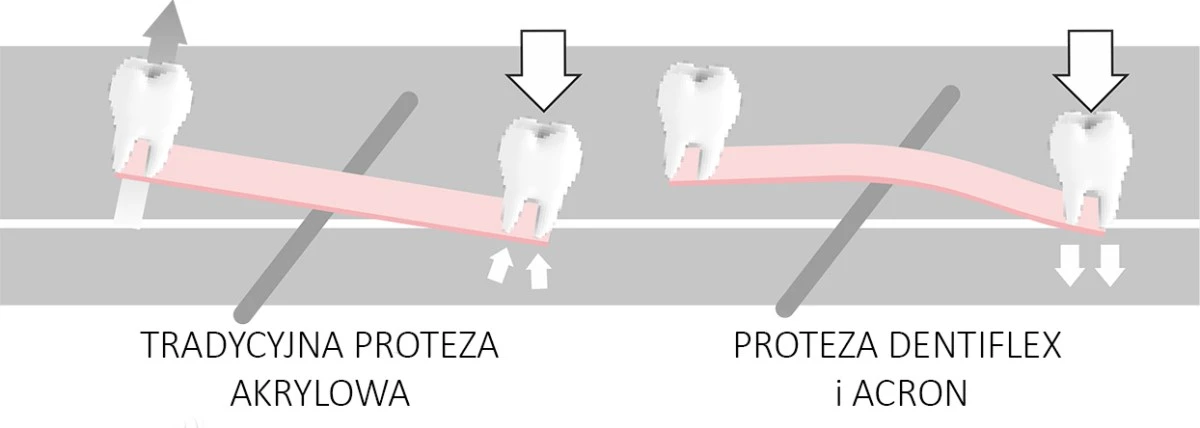

Nowoczesny termoplastyczny polimer zaprojektowany przez polskich naukowców specjalnie do wykonywania płyt protez zębowych.

BEZPIECZNY DLA PRZYZĘBIA

REDUKUJE OSIADANIE PROTEZ